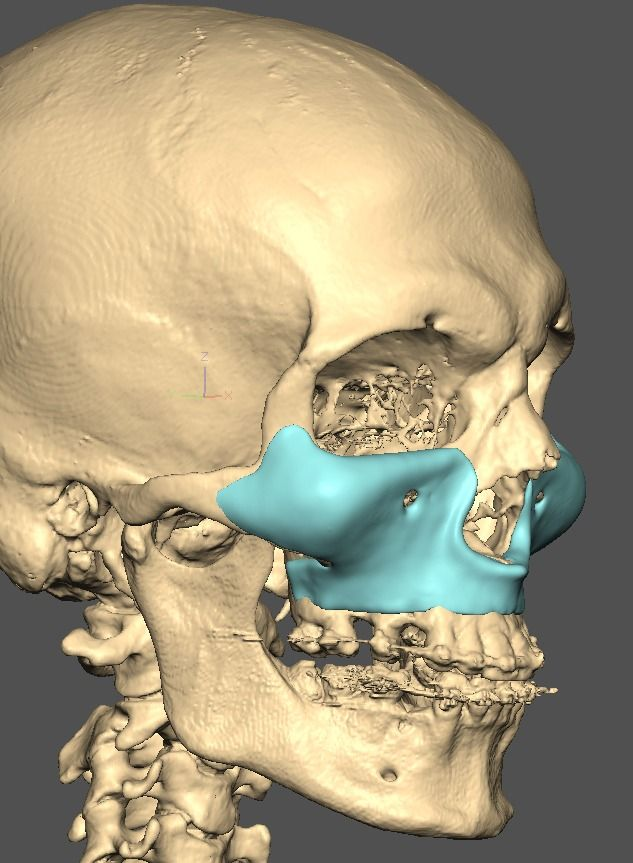

A lot changed since the initial design

current

It's going to be split into either 5 or 7 pieces.

current

It's going to be split into either 5 or 7 pieces.